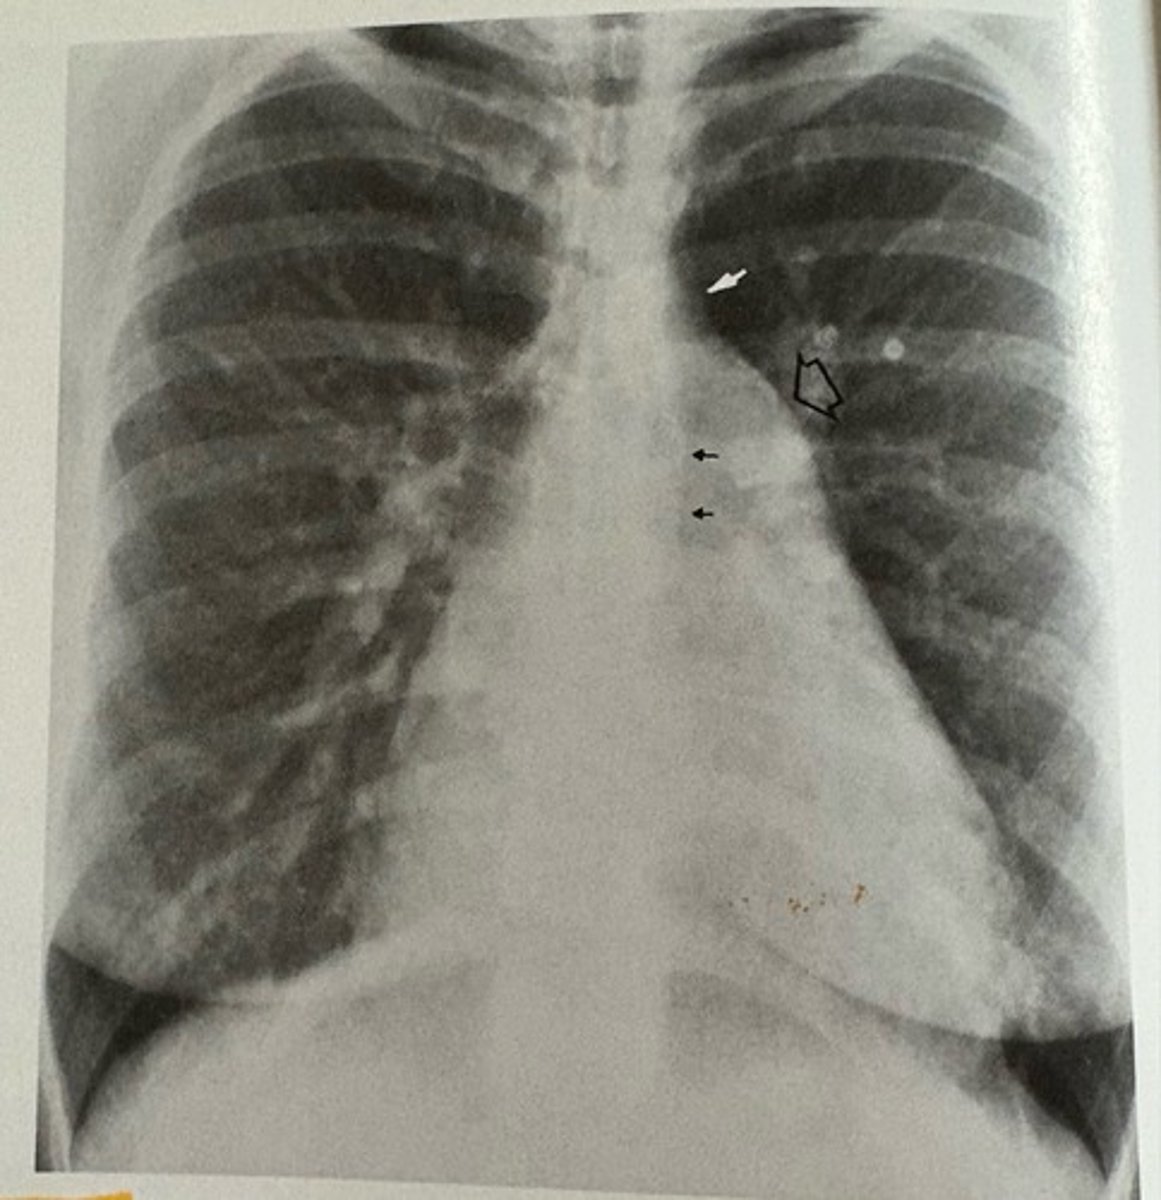

prosthetic aortic and mitral valves

what pathology is present?